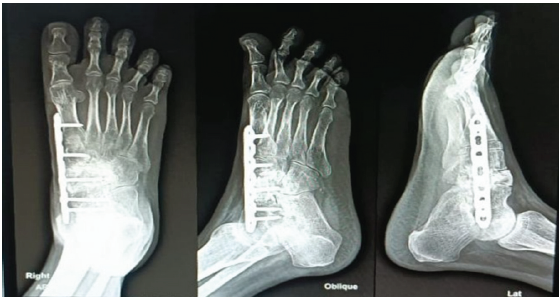

After the diagnosis of GCT was established, the patient was prepared for excision of the lesion using curettage and chemical cauterization. To impart more stable fixation and to fill the void of excision, bone grafting along with plate (3.5 mm combihole plate) fixation was done (Fig. 6, 7).

Figure 7: Immediate post-operative X-rays.

Denosumab leads to downsizing of the tumor and leads to fibrosis of the margin and inhibiting progress of the disease [4,5]; hence, a planned resection may become less morbid when preoperative denosumab is administered [6]. There is no confirmation of improved local control post-surgery, but more importantly, no increase in recurrence rates has been confirmed either [7]. En-bloc resection of GCTB, especially in the case of soft-tissue involvement, can be facilitated by a neoadjuvant denosumab regimen. The optimal treatment duration and maintenance dose and interval of denosumab in unresectable disease are still under analysis [8,9]. After stopping denosumab, the incidence was increased which was noted in few studies [10] (Fig. 8, 9).

Figure 8: 8-month follow-up X-rays.